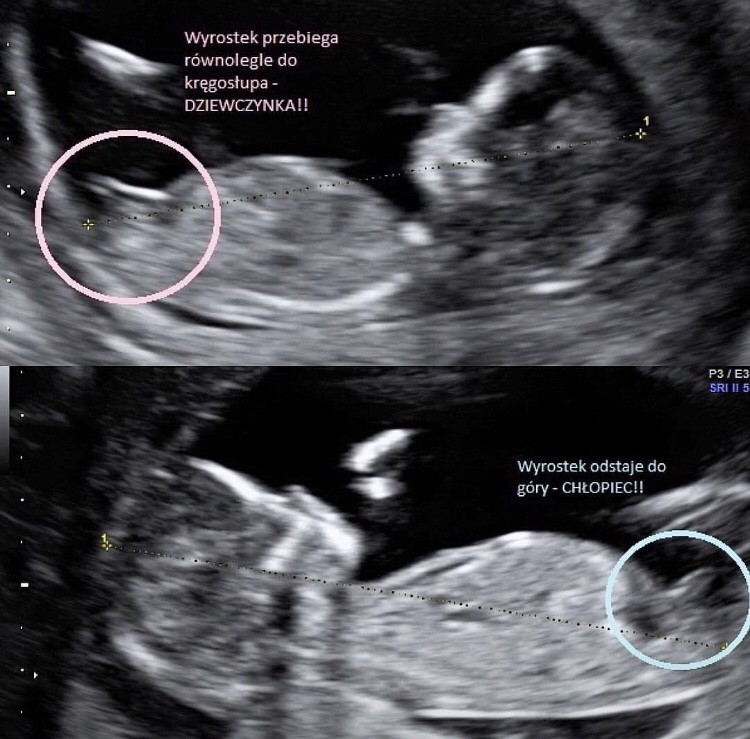

@Kasiaparasia mowa o wyrostku płciowym :) Zobacz załącznik 1057199

Myślałam ze jak kalendarze chińskie są brane na poważnie to taki wyrostek robaczkowy nie jest gorszy Hahaha :)